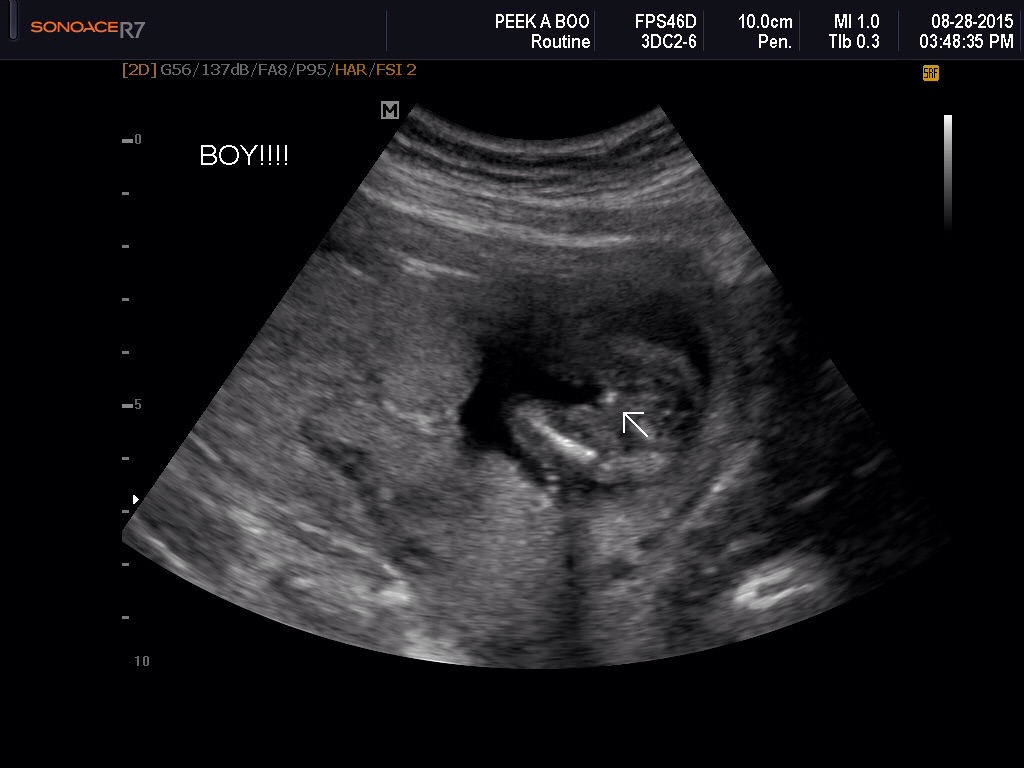

I had a gender scan at 16 weeks and they seemed confident it was a boy, now, at 26 weeks they're saying girl?! I know the three lines are there but could it be scrotum? It looks really different than what my DD's looked like!!! Thanks for any input!!Attachment 28358